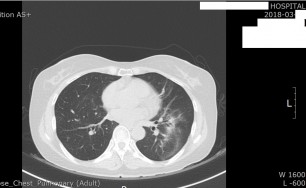

이러한 면역체계의 과민 반응이 기관지에 생기면 기관지벽이 두꺼워지고 그로 인해서 직경이 좁아지게 됩니다.

즉 천식은 기도 통로가 좁아지면 공기가 원활하게 지나가지 못하므로 호흡이 어려워져서 기침, 천식음(쌕쌕 거리는 소리), 호흡곤란, 가슴답답 등이 반복적으로 발생하는 질환입니다.